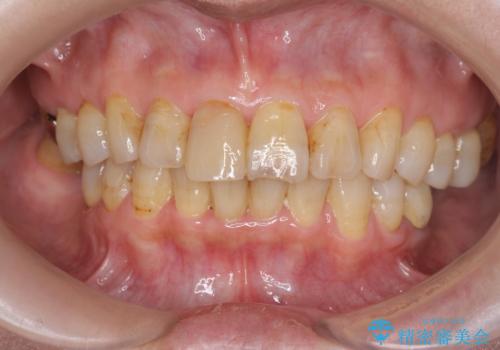

色調の変化が少なく、長期的な予後を見込めるジルコニアクラウンで天然歯を模した審美性の回復を計画します。

当法人でご提案できる最上位クラスのジルコニアクラウンです。

透明感や周囲の歯との色の調和に大変ご満足いただけました。